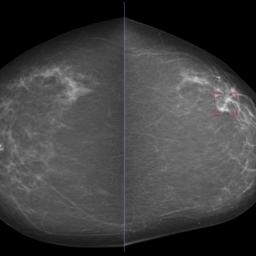

Brustkrebs: KI gibt verlässlich Entwarnung bei falschen Diagnosen

Laut einer neuen Studie kann künstliche Intelligenz mehr als die Hälfte der Scans automatisch durchführen. Das reduziert die Arbeitsbelastung von Radiologen.​